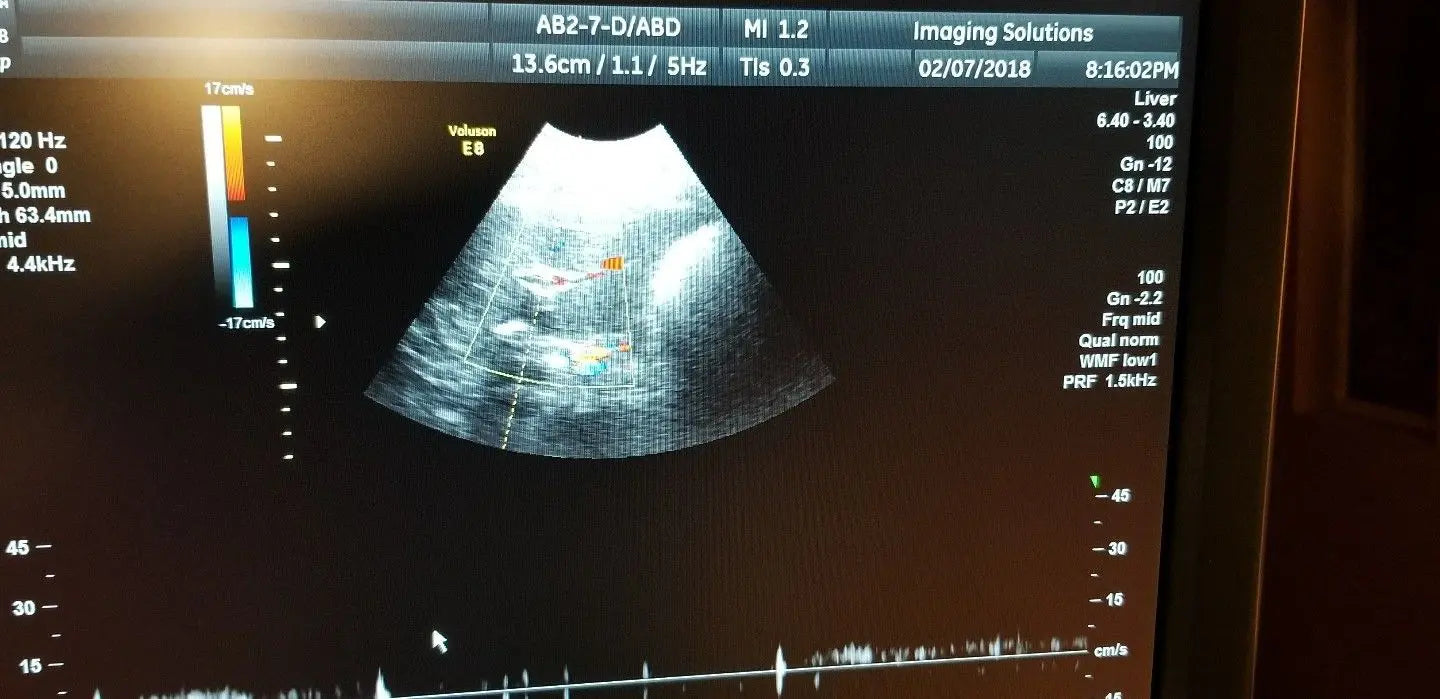

Exceptional Imaging Quality

The GE ultrasound probe, model AB2-7-D, is renowned for its superior imaging capabilities. It features advanced transducer technology that provides high-definition images, which are crucial for accurate diagnoses. This probe excels in various medical applications, including obstetrics and gynecology, allowing medical professionals to visualize internal structures clearly. Because of its cutting-edge design, clinicians can rely on the GE ultrasound probe for precise assessments, enhancing patient outcomes significantly.